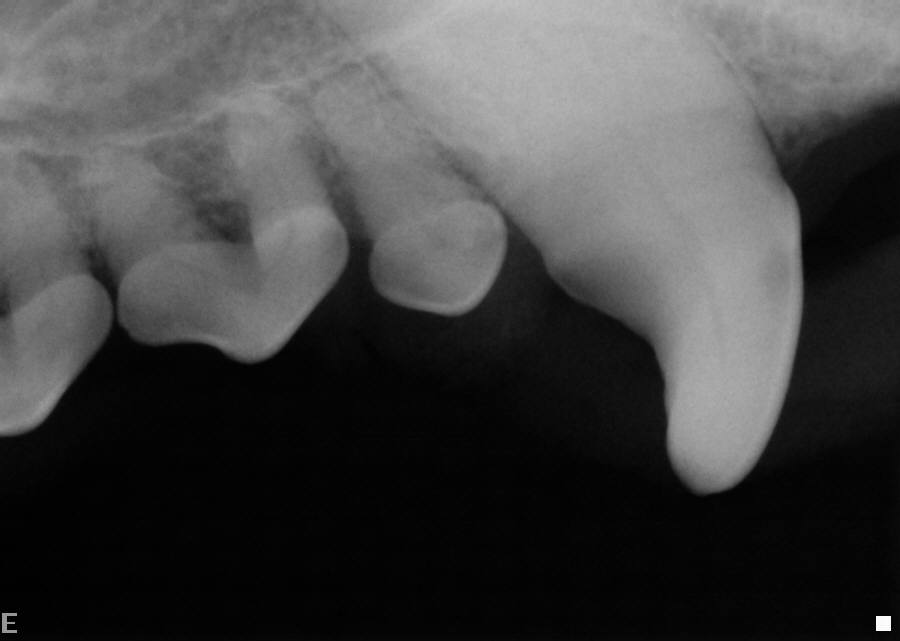

Dental X-ray Right Bitewing

-

Dental X-ray Left Mandibular